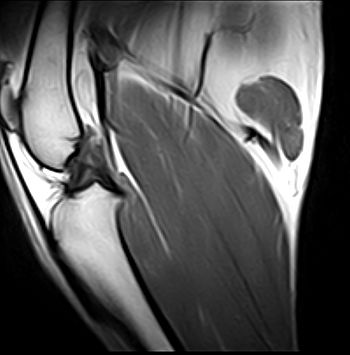

When dogs receive injuries to their knees, it is often in the form of a Dog Luxating Patella or a ruptured cruciate ligament. There are three bones that comprise the knee. The femur, the bone the goes down from the hip, the Tibia, which is the bone found between the knee and ankle, and the Patella, which is known as the kneecap. Lots of ligaments are used to join these bones together. When two ligaments cross in a joint from the femur to the tibia, they are known as cruciate ligaments. The anterior and posterior cruciate ligaments are responsible for keeping the femur and tibia ends from rubbing painfully against one another.

If the anterior cruciate ligament ruptures, then the joint cannot be used, allowing the tibia and femur to rub against one other. This usually happens when the animal twists on his back leg. This puts extraordinary amounts of pressure on the ligament, resulting in tearing.

A veterinarian will make a diagnosis of a torn cruciate ligament by watching the way the dog walks and moves. Using a specific manner, the vet will grab the femur and tibia, and determine if the bones are moving in a way known as the drawer sign. It is referred to as the drawer sign, because the way the femur and tibia move in direct relation to each other is much like the pushing and pulling of a cabinet drawer. Dogs that are in a lot of pain, or too stressed, often will have muscles that are too tense to determine the drawer sign, so they may have to be sedated to allow the muscles to relax enough for a proper diagnosis.